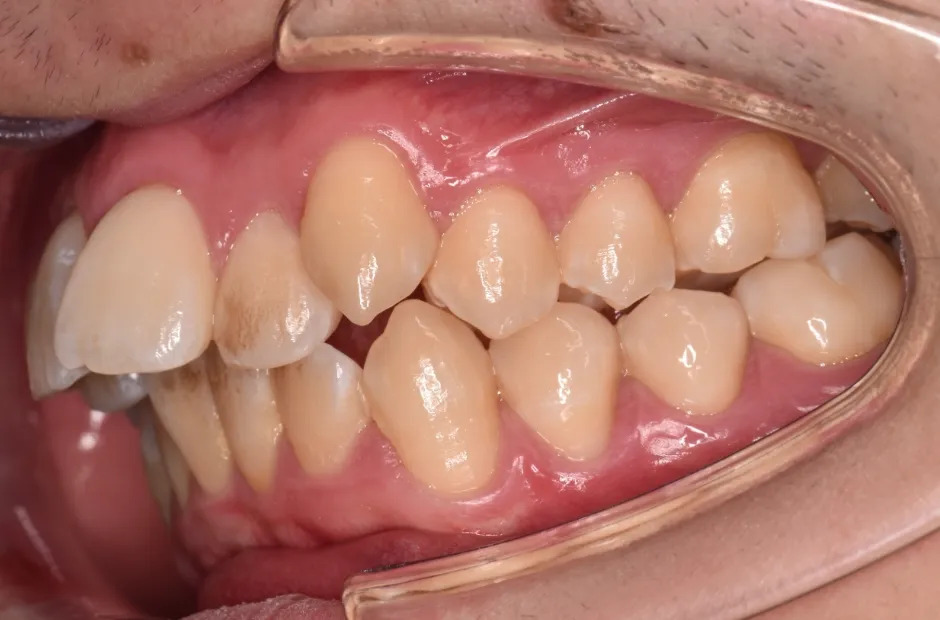

治療症例

ブラケット矯正

前歯部反対咬合

| 診断名・主訴 | 前歯部反対咬合 |

|---|---|

| 年齢・性別 | 14歳・男性 |

| 治療期間・回数 | 1年2か月 |

| 治療に用いた主な装置 | ブラケット矯正 |

| 抜歯部位 | なし |

| 治療費 | 60万円(税抜) |

| リスク・副作用 | 装置による違和感・疼痛・歯肉退縮・歯根吸収・虫歯のリスクなど |

治療後